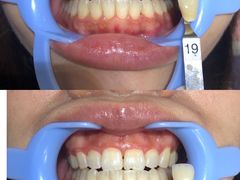

• Dr.Z dental仁康种植矫正中心

• -Dr.Z dental仁康种植矫正中心

dszchupas | 20-11-19